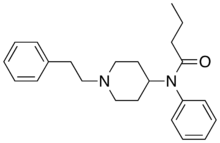

Chemical structures of various fentanyl analogues

Butyrfentanyl (Bu-F, BUF) | N-(1-(2-Phenylethyl)-4-piperidinyl)-N-phenylbutyramide | 1169-70-6 |

|